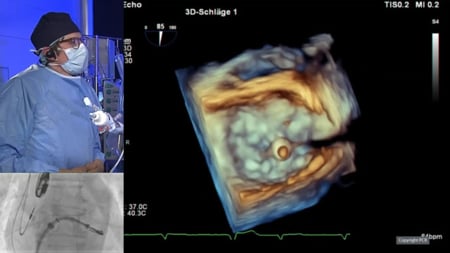

Mitral transcatheter edge-to-edge repair - LIVE Case

29 Sep 2025 – From PCR Gulf Valves 2025

This live educational session from Prince Sultan Cardiac Center in Riyadh offers an in-depth look at mitral transcatheter edge-to-edge repair (TEER) with MitraClip. Learn best practices for patient selection, imaging analysis, operator strategies, and witness a live case procedure to optimize clinical outcomes.

LIVE Educational Case from...